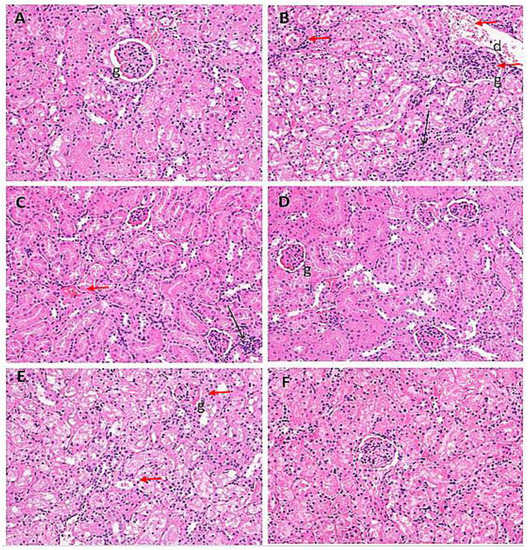

2.7. Histological Evaluation of Kidney Samples

| Treatment Groups | I | II | III | IV | V | VI |

|---|---|---|---|---|---|---|

| Oedematous glomeruli | − | +++ | ++ | − | +++ | − |

| Hemorrhage | − | ++ | ++ | − | − | − |

| Infiltration of inflammatory cells | − | +++ | ++ | + | ++ | + |

| Hyaline casts | − | ++ | ++ | − | ++ | + |

| Disintegrated nucleus | − | + | − | − | − | − |